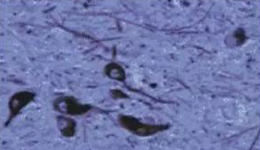

PD的病理改变主要位于黑质,而且变性、脱落的细胞主要是致密带的多巴胺能细胞。此外,蓝斑核、迷走神经背核、中缝核等脑干中含有色素的神经细胞群也有明显的变性,基底节核也有明显的病变。PD的另一个病理特点是变性区残存的神经元胞浆内的Lewy小体,但Lewy小体的意义未明。最新的研究发现α-突触核蛋白突变在Lewy小体与PD的病因有关,但近年来的研究发现Lewy小体是细胞正常成分-神经元丝构成。Lewy小体不是PD特有,Lewy体痴呆也可以看到。

正常人:黑质神经元存在

PD患者黑质神经元丢失